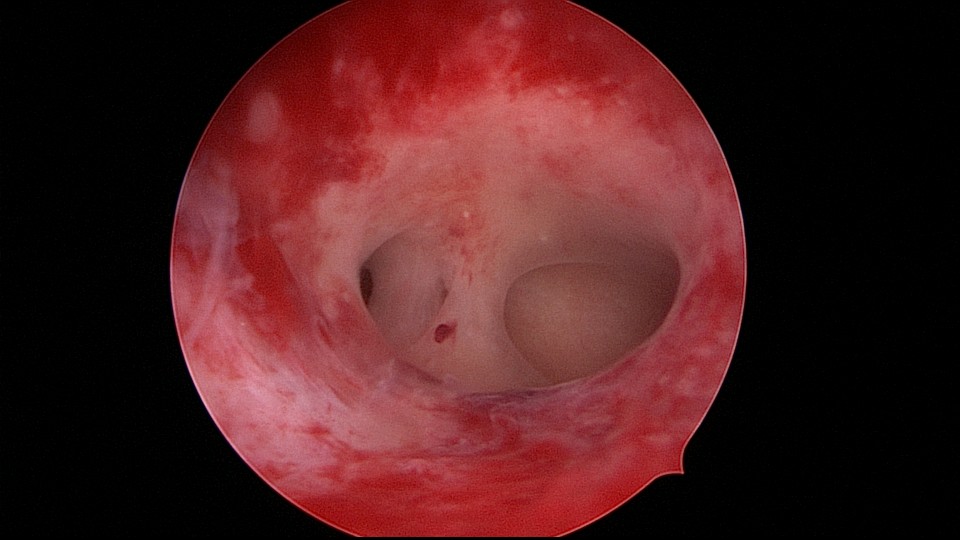

患者35岁,G5P0,继发不孕10年,10年前外院开腹宫外孕手术1次,试管失败1次。外院B超提示宫腔粘连,2021年4月在成都西囡妇科医院做宫腔镜检查,发现宫腔粘连。2021年11月到我院做宫腔镜分粘手术,术中见宫腔两侧及右侧宫角致密粘连,内膜片状充血,单极电切分粘,恢复宫腔形态,显露双侧输卵管开口。2021年12月宫腔镜二探取球囊,宫腔形态正常,双侧输卵管开口可见。分粘后再次试管成功,足月分娩。现40岁,G6P1。